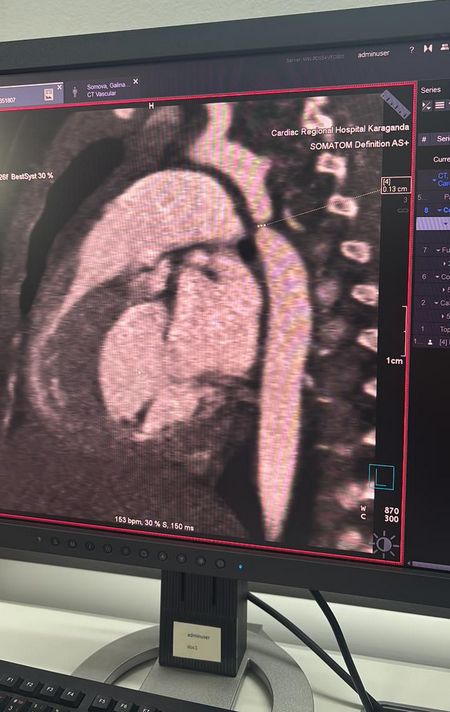

История началась с диагноза, который не предвещал серьёзной угрозы. Девочку госпитализировали с пневмонией в многопрофильную больницу №1. Однако во время обследования врачи выявили опасную патологию — критическую коарктацию аорты. Это врождённый порок сердца, при котором происходит резкое сужение главного сосуда организма и нарушается кровоток.

Операция продолжалась почти пять часов. Врачи выполнили резекцию коарктации аорты с наложением анастомоза «конец в конец», полностью восстановив кровоток. Во время вмешательства также выявили открытый артериальный проток — его успешно легировали.